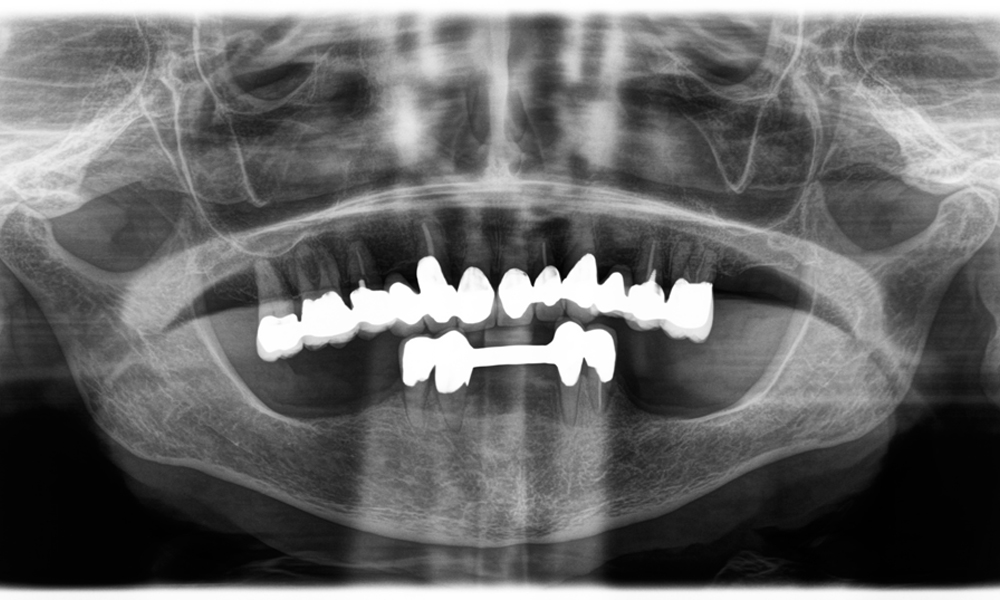

A x-ray, showing teeth and a zirconia crown, in front of a black background.

Figure 2: Replacement of a damaged zirconia crown: Precise removal and renewal of a damaged zirconia crown on tooth 6 with minimal material loss.

A second case highlighting the clinical capabilities of the Power Edition involved the replacement of a damaged zirconia crown in a 63-year-old patient. The patient presented with a chipped veneer on her 20-year-old zirconia crown on tooth 6. Despite the posterior location, the patient found the defect bothersome and requested a new restoration.

The Power Edition enabled precise sectioning, with the increased torque and enhanced cooling contributing to the controlled removal of the crown without significant material loss. The chucking system and enhanced torque proved to be essential in this process.